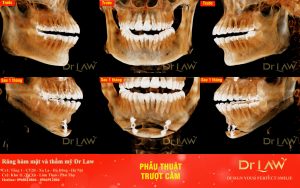

Phẫu thuật trượt cằm: Đây là phương pháp can thiệp trực tiếp vào vùng xương cằm. Cụ thể là vùng xương cằm sẽ được cắt rời, và điều chỉnh ra trước, vào sau hoặc sang 2 bên, sao cho cân xứng nhất với khuôn mặt. sau đó được cố định bằng nẹp vít. Với phương pháp này sẽ thực hiện gây mê để đảm bảo cho bệnh nhân không đau, và an toàn.